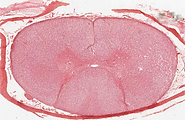

Medula espinal​ - Ganglio Cerebroespinal

Medula espinal

Medula Espinal- Neuronas multipolares- 40x

Medula Espinal y ganglio espinal- Tricromica de masson- 20X

Medula Espinal l- H-E- 40X